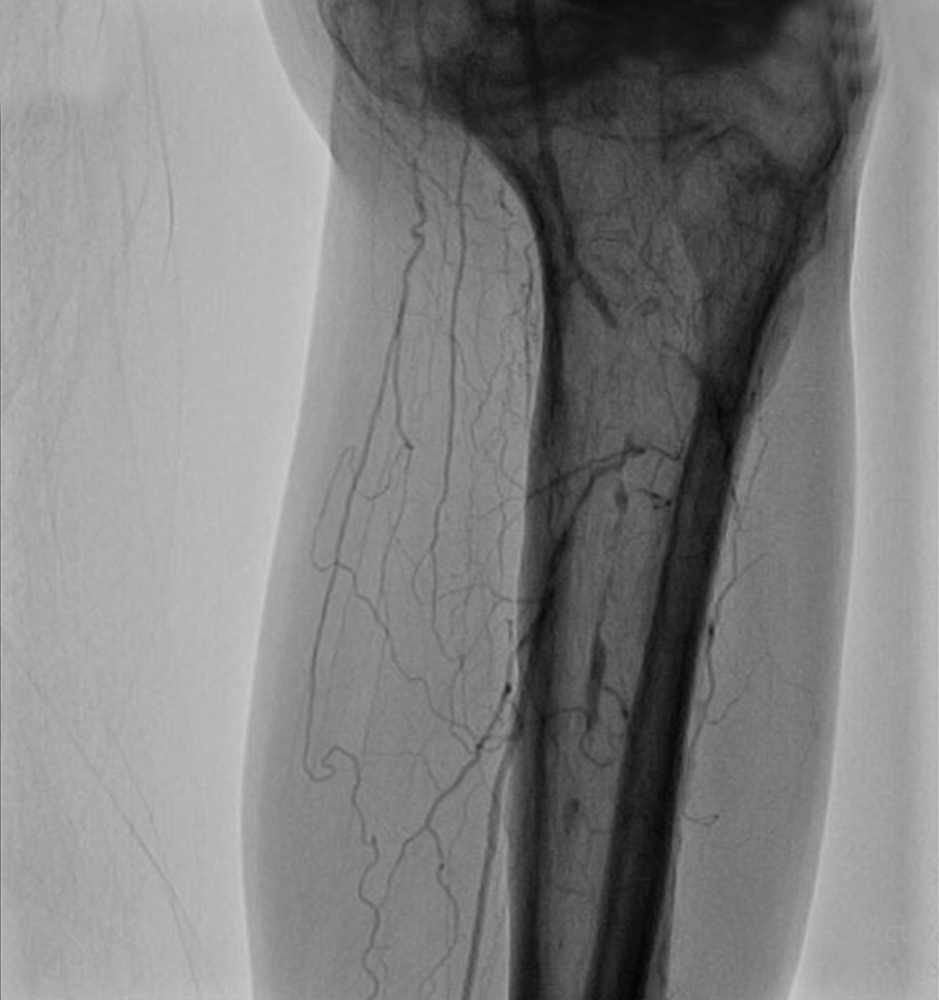

Tibial Artery Occlusion

Endovascular treatment of infrapopliteal lesions has become more common and techniques continue to improve, Vascular Specialists are exploring use of endovascular therapy in more distal arterial territories.

The pedal loop technique, allows for intervention on the distal tibial arteries and the pedal/plantar loop while only using one access site which can improve transcutaneous oxygen tension in the foot at 15 days.  The angiosome concept has gained popularity as an approach to improve limb salvage, whereby the target vessels for revascularization are chosen based on the angiosome in which the wound is located. The limb salvage was 86% when wound angiosomes were directly revascularized versus 69% for indirect revascuarlization.

Treatment options in Endovascular Surgery are Infrapopliteal Angioplasty, Infrapopliteal Angioplasty and Stenting, Drug-Eluting Stents, Excisional atherectomy. These techniques mentioned above are deployed appropriately to get the best outcomes for limb salvage.

PREOPERATIVE ASSESSMENT AND PREOPERATIVE IMAGING with Duplex scan of lower limb arterial system,CT angiogram and In most patients, standard arteriography is still the “gold standard. If endoluminal therapy is the case, Endoluminal/Endo Vascular treatment at the time of diagnostic arteriography is  performed.